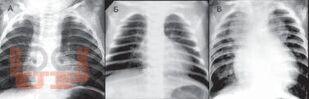

Книга посвящена одному из важнейших разделов детской кардиологии - врожденным порокам сердца. В общей части рассмотрены особенности нормального кровообращения у плода и новорожденного, а также его изменения при врожденной патологии сердца; кроме того, читатель знакомится со специальной терминологией. В разделе частной патологии подробно представлены все основные пороки, встречающиеся в практике детских врачей, алгоритмы их диагностики, современные возможности терапевтического и хирургического лечения; изложены вопросы послеоперационного наблюдения за пациентами. Издание содержит более 140 рисунков и схем, иллюстрирующих ключевые расстройства гемодинамики, методы исследования сердца и наиболее распространенные операции.